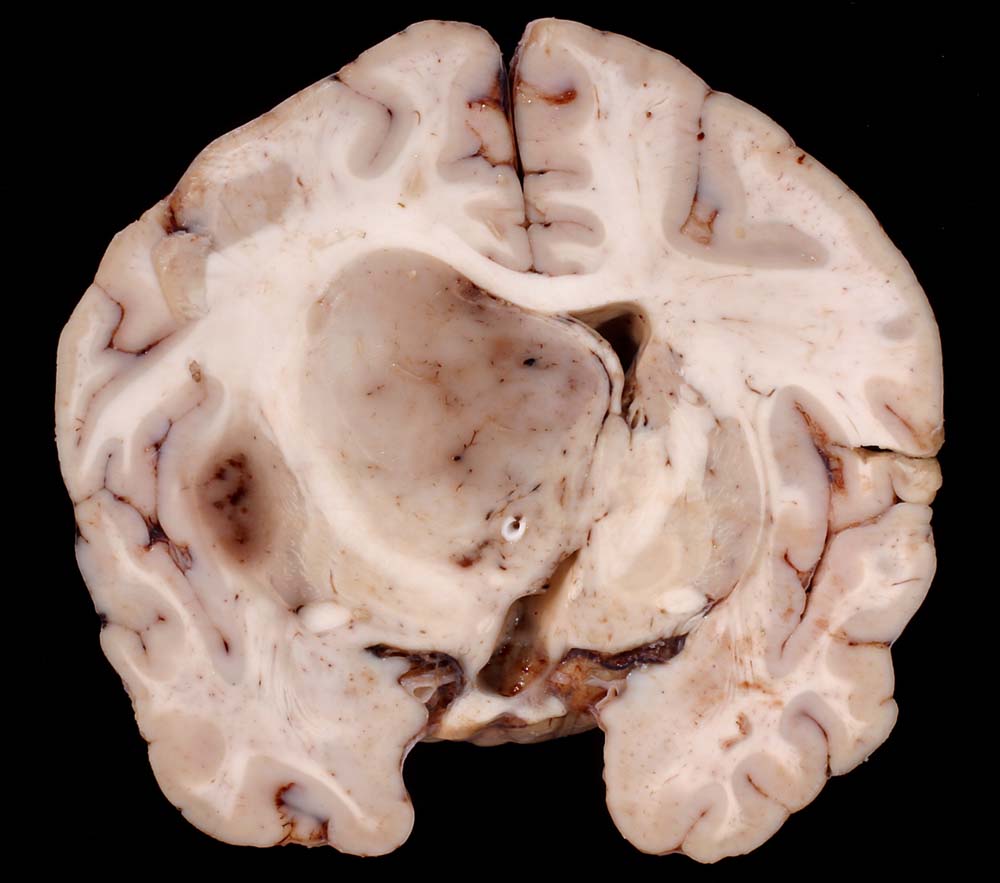

Anaplastisches Oligodendrogliom

maligner Tumor

Hirn parietal

Gräuliches Tumorgewebe verschiebt die Mittellinie stark zur Gegenseite und komprimiert den Seitenventrikel.

Anaplastisches Oligodendrogliom Grad III nach WHO.

Thalamus-Tumor. Hydrocephalus bei Tumoreinblutung. Einklemmung.